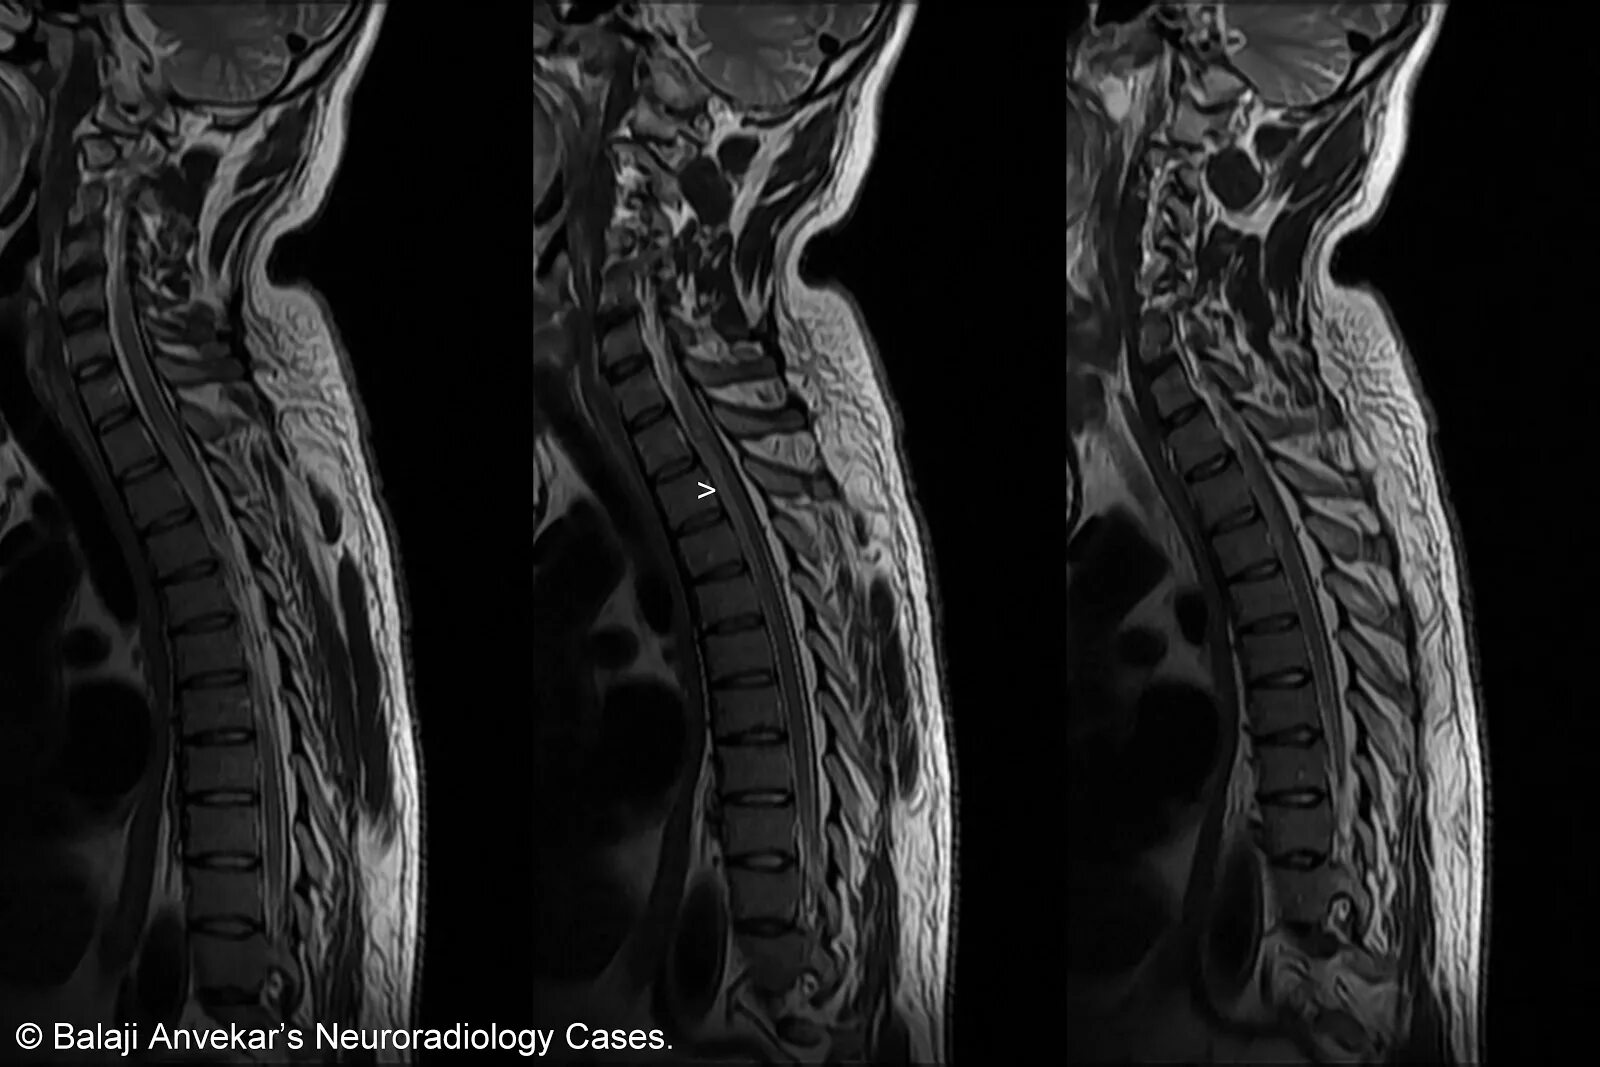

Spine mri